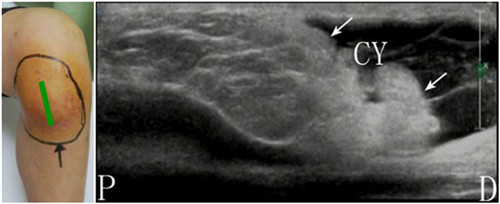

2018年7月,重医附属康复医院骨关节康复科开始开展肌骨超声诊疗的项目,是重庆康复领域领先使用该技术的单位之一。诊疗覆盖的疾病包括:膝关节炎、膝关节积液、膝内外侧副韧带松弛、肱二头肌长头肌腱炎、肩峰下滑囊炎、冈上肌腱损伤、肩胛下肌损伤、盂肱关节炎、胸锁关节炎、肘关节积液、肱骨外上髁炎、腕管综合征、腕部肌腱炎、足底筋膜炎、踝关节积液、踝关节肌腱炎、跟腱炎等系列软组织炎症疼痛疾病。迄今为止已完成150余人次诊疗,患者反映效果良好,也为广大患者带来了福音!